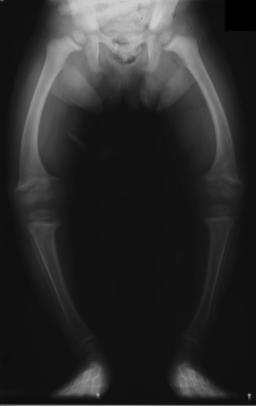

| تصوير بالأشعة لمريض بالرخد في الثانية من عمره، with a marked genu varum (bowing of the femurs) and decreased bone opacity, suggesting poor bone mineralization. | |

- الأطفال الصغار: تقوس الساقين (ركبة فحجاء)[4]

An X-ray or radiograph of an advanced sufferer from rickets tends to present in a classic way: bow legs (outward curve of long bone of the legs) and a deformed chest. Changes in the skull also occur causing a distinctive "square headed" appearance (Caput Quadratum). These deformities persist into adult life if not treated. Long-term consequences include permanent bends or disfiguration of the long bones, and a curved back.[5]

يصبح اتساع المشاش في المعصمين وعنقي القدم (النهايات السفلية للزند والكعبرة وعظم الفخذ والشظية)، واضحاً للعيان باستمرار الحدثية الرخدية، ويؤدي نقص تكلس العظام خاصة بعد بدء الطفل بالوقوف والمشي إلى تقوسات بالطرفين السفليين وتبدلات في الركبتين فيحدث الروح والفحج.